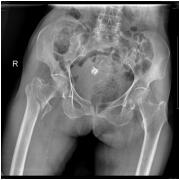

莆田盛兴医院骨科又成功完成一例百岁老人骨折手术